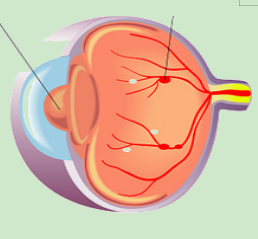

1.png

正常视网膜血管

2.png

糖网的视网膜血管渗漏